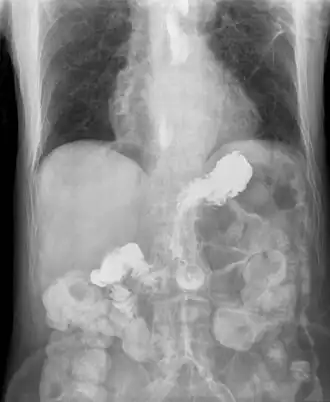

Röntgenfoto met reflux vanuit de maag naar slokdarm